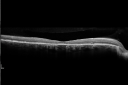

Acute Posterior Multifocal Placoid Pigment Epitheliopathy - APMPPE - SD-OCT 1310 views 25-year-old man with one and half weeks ago he woke up with night chills. Also around that time his joints started hurting him. He also has headaches, although the headache at this point is not severe. His vision has been changing for about the last week and a half. He sees some spots in his vision and they are blurred spots. They are not in the central vision.

VISUAL ACUITY: OD 20/32, OS 20/32

Acute Posterior Multifocal Placoid Pigment Epitheliopathy - APMPPE - SD-OCT 1275 views 25-year-old man with one and half weeks ago he woke up with night chills. Also around that time his joints started hurting him. He also has headaches, although the headache at this point is not severe. His vision has been changing for about the last week and a half. He sees some spots in his vision and they are blurred spots. They are not in the central vision.